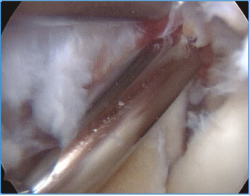

Método: hemos revisado 38 pacientes con codo rígido postraumático o degenerativo que se trataron mediante artrolisis artroscópica entre 2013 y 2016, con un seguimiento medio de 25 meses (38-15). Según la etiología de la rigidez, clasificamos a los pacientes en 2 grupos: grupo 1, los pacientes con rigidez por patología degenerativa del codo, y grupo 2, los pacientes con rigidez postraumática. Clasificamos la rigidez siguiendo la escala de Morrey y utilizamos la escala funcional Mayo Elbow Performance Index (MEPI), que evalúa el dolor, la movilidad, la estabilidad y la función del codo pre- y postoperatoriamente. Describimos los procedimientos artroscópicos realizados en cada paciente, que incluyen la sinovectomía, el desbridamiento de tejido fibroso, la capsulectomía anterior y/o posterior, la resección de osteofitos en la parte anterior y posterior del codo, la extirpación de cuerpos libres y la liberación “abierta” del nervio cubital.

Method: a review was performed on 38 patients with stiff elbow due to degenerative or post-traumatic reasons, and who were treated by arthroscopic arthrolysis between 2013 and 2016, with a mean follow-up of 25 months (38-15). Elbow stiffness was classified following the Morrey scale and the Mayo Elbow Performance Index (MEPI) functional scale was used to evaluate pain, mobility, stability and elbow function pre- and post-operatively. The arthroscopic procedures performed on each patient are described, including synovectomy, debridement of fibrous tissue, anterior and/or posterior capsulotomy, resection of osteophytes in the anterior and posterior part of the elbow, extirpation of loose bodies and open release of the ulnar nerve.